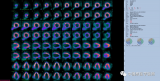

侯露:177Lu标记新型成纤维细胞活化蛋白抑制剂靶向治疗放射性碘难治性分化型甲状腺癌的初步研究

放射性示踪剂[68Ga] Ga-DOTA.SA.FAPi在转移病灶明显浓聚,同时口腔粘膜、唾液腺、肝脏、胰腺、胆囊、结肠和肾脏存在一定的生理性摄取。使用[177Lu]Lu-DOTAGA.(SA.FAPi)2治疗后直到第168h仍可见主要病灶的放射性浓聚。患者治疗前后出现了明显的分子反应,PET/CT显示主要病灶的大小和SUVmax都有减小和降低,患者的Tg水平也从>300000 ng/mL下降到6586,达到了显著的生化反应;该患者治疗前后VASmax评分也从10分下降到4分,临床症状得到明显的缓解。 2022-09-25 靶向治疗放射诊疗